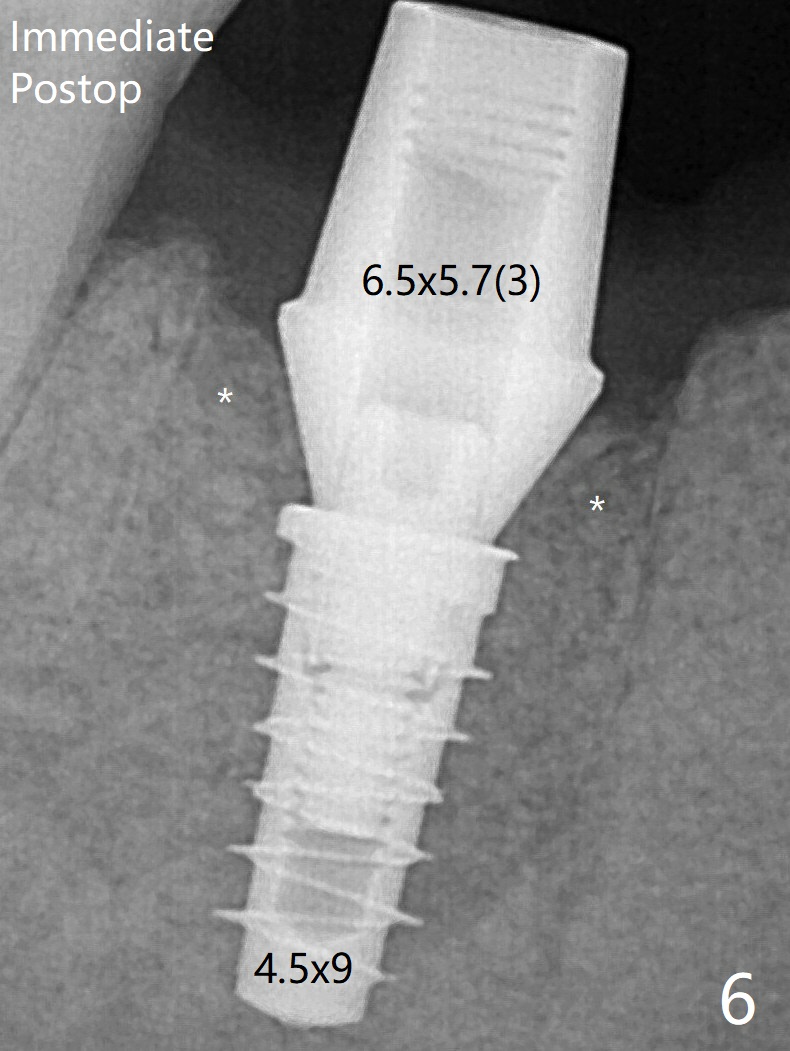

In spite of the immediate provisional, the abutment margin is substantially subgingival mesial 4 months postop, extremely difficult to take impression.  A smaller diameter and longer cuff abutment is placed (Fig.15).